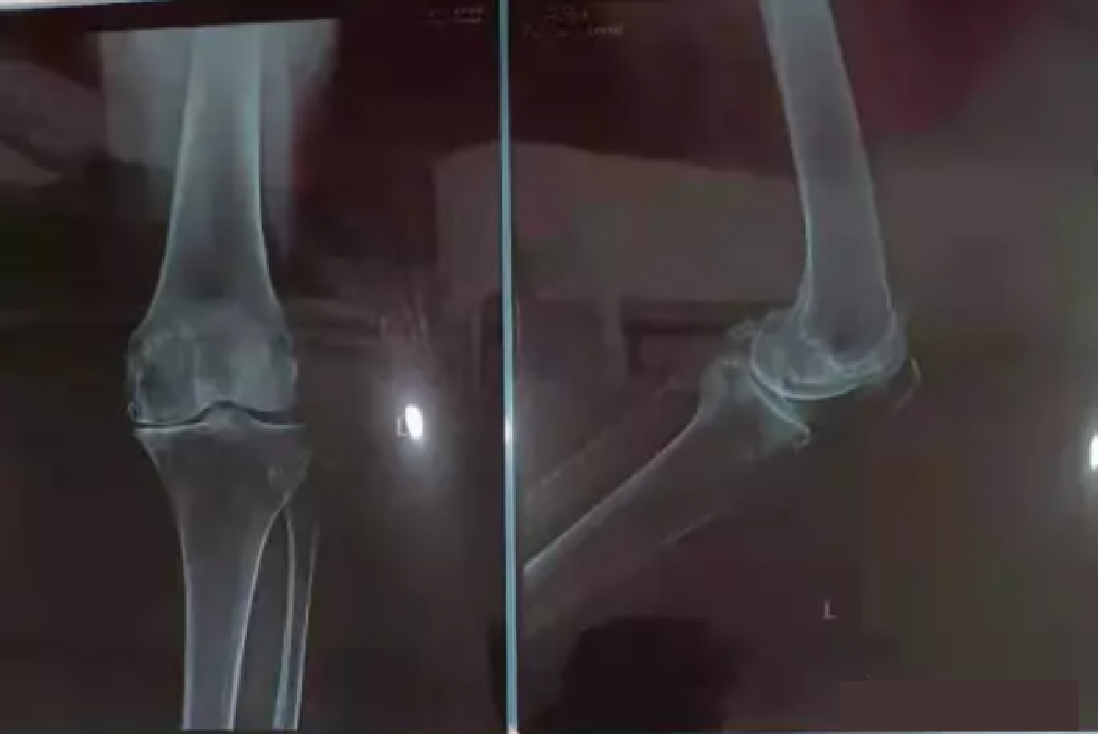

圖片

“李女(nǚ)士的(de)膝關節X光(guāng)片”